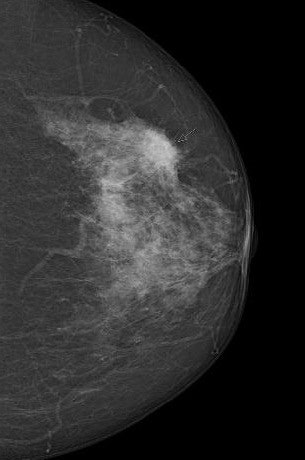

We need to start by explaining exactly what screening is: It's an initial search method that distinguishes between "normal" and "abnormal." An "abnormal" finding currently means the diagnosis has to be confirmed using additional methods. A screening mammogram doesn't clearly tell us whether the abnormality in the image is malignant, or why it's abnormal. If we eventually find it's benign, or there hasn't actually been a tissue change, we call it a false positive.

Any examination method can overlook a tumor, and this is something else you have to be open about. It's called a false-negative finding, and we can minimize it by using modern, proven mammography techniques and by providing special training for all screening teams, including radiologists and doctors. This is also why we use dual diagnosis: Each mammogram must be separately analyzed by at least two doctors. Two pairs of eyes are better than one, and this method gives at least a 15% increase in tumor detection rates than with one doctor.

And mammograms have their limitations when it comes to particularly dense tissue?

Yes, for women on the program who are ages 50 and older and have very dense type 4 breast tissue, although they really are the exception. Digital mammography, which is now standard in screening, penetrates dense tissue much better than analog x-rays 10 years ago.

We've just carried out a study in Münster of the density at which mammographic sensitivity declines. We found that contrary to what has been written elsewhere, sensitivity starts declining only with extremely dense type 4 tissue. We found no significant difference in sensitivity for women with a density of 1 to 3. Our study found the two-year interval screening mammogram program was significantly below average in only five percent of women. We need to consider giving them additional screening.